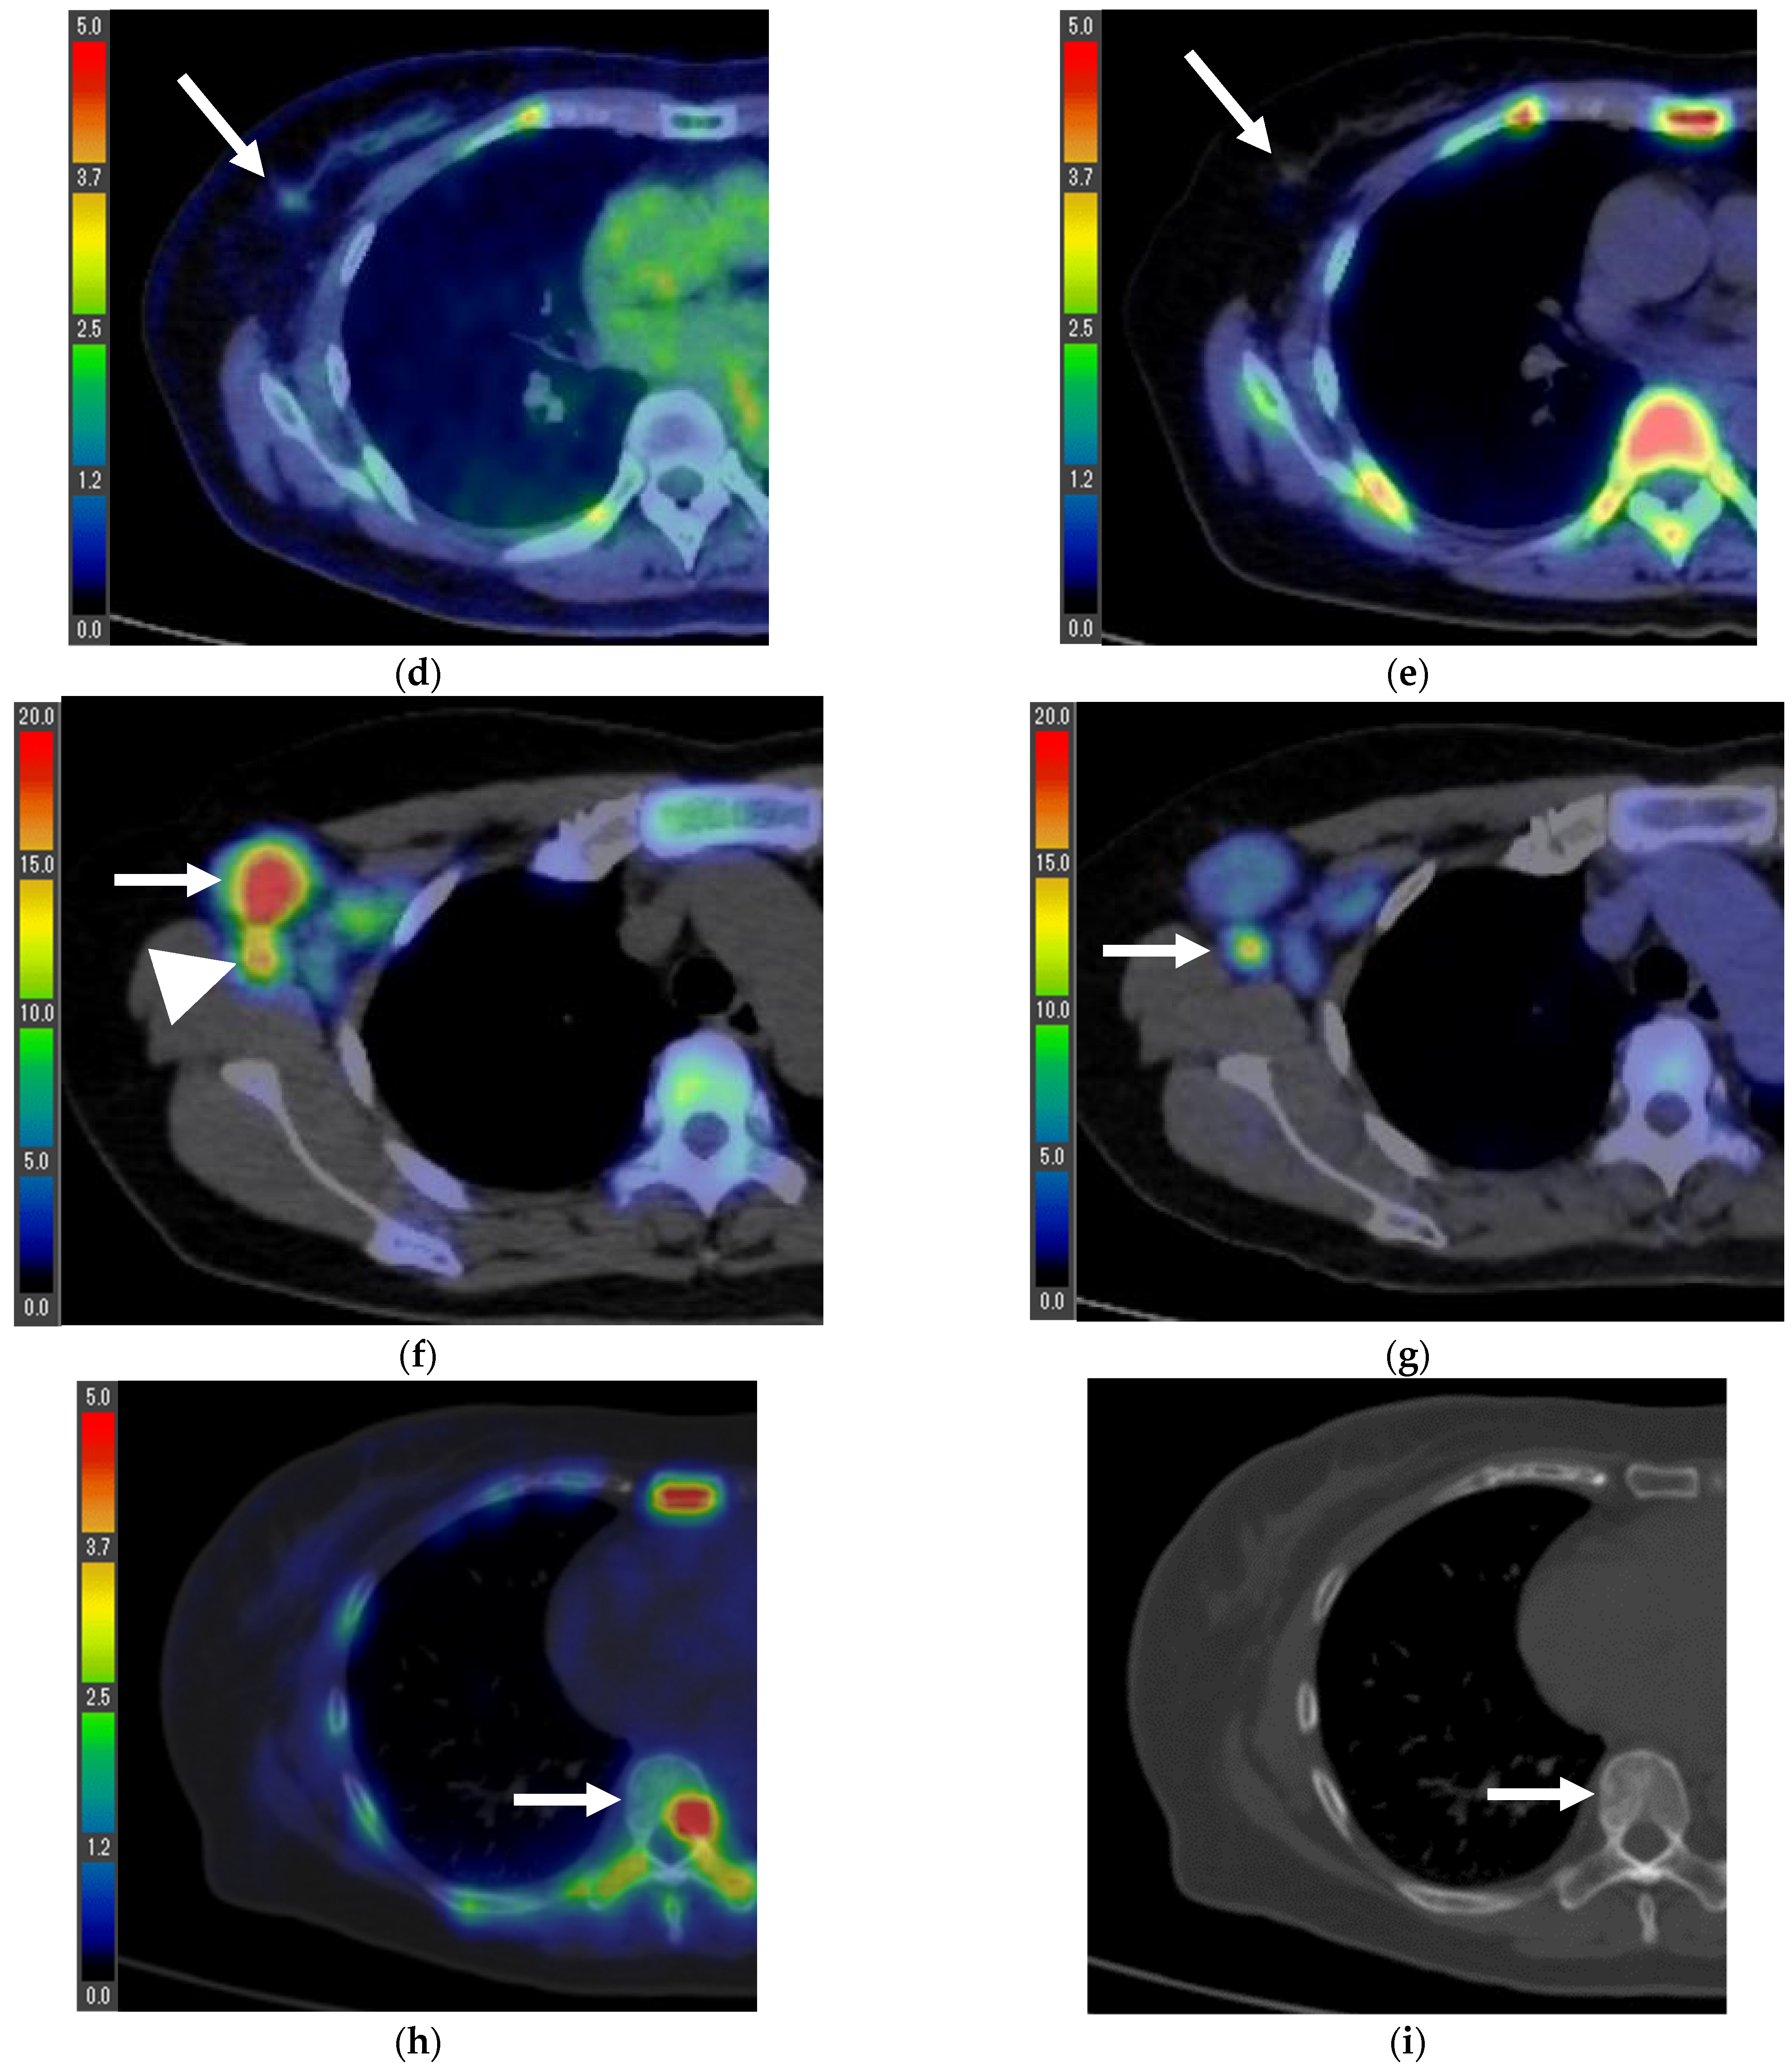

| 4 | 0.4 | 1.5 | 16.7 * | 14.2 * | T1bN3aM1 *** (Lymph node and bone metastases) | Invasive ductal carcinoma | Data loss | + | + | − | Data loss |

| 5 | 3.8 | 8.3 | 1.8 | 6.3 | T2N3bM0 *** | Invasive ductal carcinoma | 1 | + | + | − | 25 |

| 6 | 4.8 | 8.4 | 1.4 | 3.2 | T4bN1M1 *** (Lumbar vertebra metastasis) | Invasive ductal carcinoma | 1 | + | + | − | 8.9 |

| 7 **** | 7.0 | 10.1 | 1.2 | 0.7 | T4bN0M0 | Invasive ductal carcinoma | Data loss | − | − | + | 59 |

| 8 ***** | - | - | 1.1 | 4.1 | N3bM1 (Lymph node, lung, and bone metastases) | Invasive ductal carcinoma | 3 | + | − | + | 29.3 |